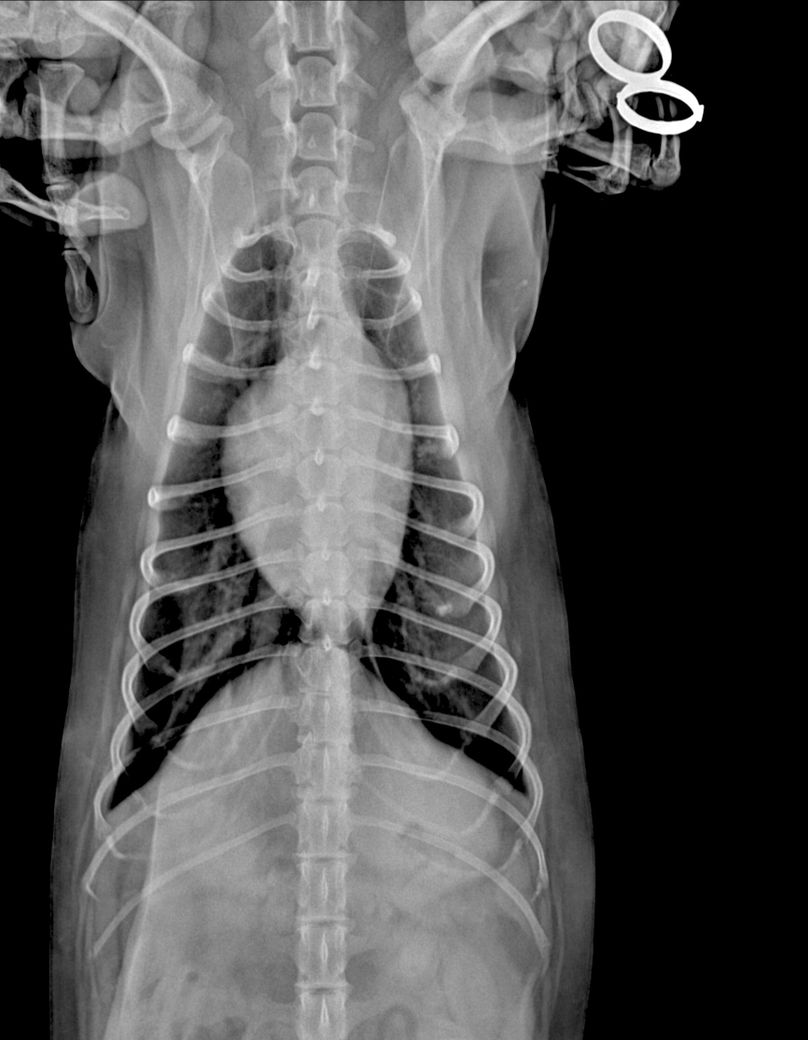

안녕하세요 강아지 건강검진을했는데 흉골이 휘었다고해서요. 첫번째사진은 1년전이고 2,3번째 사진은 이번년도 사진입니다.

혹시 이런경우 원인은 무엇인가요? 외부충격은 없었습니다..

2~3번 사진은 촬영상이 돌아가면서 흉골이 "휘어 보이는것 처럼" 보이는 것이고 실제 휜게 아닙니다. 앞에서 언급되었던 오목가슴과 같은 문제는 이 촬영상이 아닌 옆에서 촬영하는 외측상으로 판단하는것입니다.